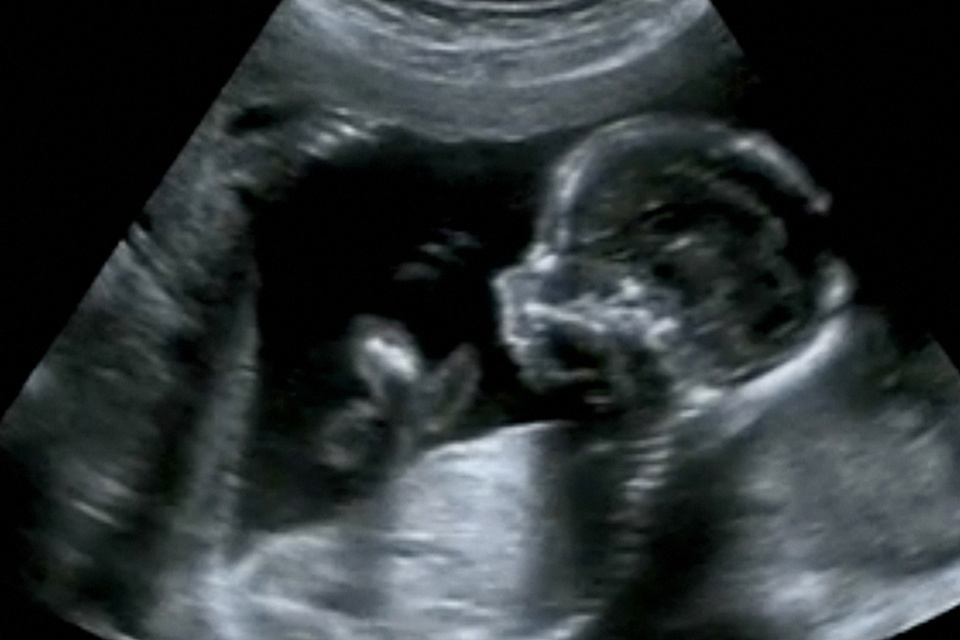

In vitale organen van ongeboren baby’s zijn er al sporen van luchtvervuiling terug te vinden. Dat blijkt uit nieuw onderzoek van Universiteit Hasselt en de Universiteit van Aberdeen, dat gepubliceerd werd in The Lancet Planetary Health. “Eerder onderzoek van ons team toonde al aan dat er in alle trimesters van de zwangerschap roetdeeltjes in de placenta terug te vinden zijn. Nu zien we dat die roetdeeltjes daar niet blijven, maar ook echt in de organen van de foetus terecht komen”, zegt prof. dr. Tim Nawrot (UHasselt).

Het is voor het eerst dat een team van wetenschappers roetdeeltjes kan detecteren in de organen van foetussen. “Dankzij de vele stalen die we ter beschikking hebben via ons geboortecohort in samenwerking met Ziekenhuis Oost Limburg in Genk, konden we eerder al ontdekken dat blootstelling aan luchtvervuiling bij zwangere vrouwen ervoor kan zorgen dat minuscule roetdeeltjes in de placenta terecht komen, nu wilden we nagaan welke impact die roetvervuiling precies kan hebben op de ontwikkeling van de foetus in de baarmoeder”, zegt prof. Tim Nawrot. “We zien nu voor het eerst dat roetdeeltjes een weg vinden tot in de organen van de foetus, waaronder de lever, de longen en zelfs de hersenen. En dat terwijl deze organen bij de ongeboren baby nog in volle ontwikkeling zijn.”

“Vooral het feit dat deze roetdeeltjes in de nog volop ontwikkelende hersenen terecht komen, is onrustwekkend”, zegt prof. dr. Paul Fowler van de Universiteit van Aberdeen, die meewerkte aan dit onderzoek. “Dit betekent dat deze nanopartikels via de hersenen in contact komen met het volledig netwerk van cellen en organen in het lichaam van de foetus en hierop kunnen inwerken.”